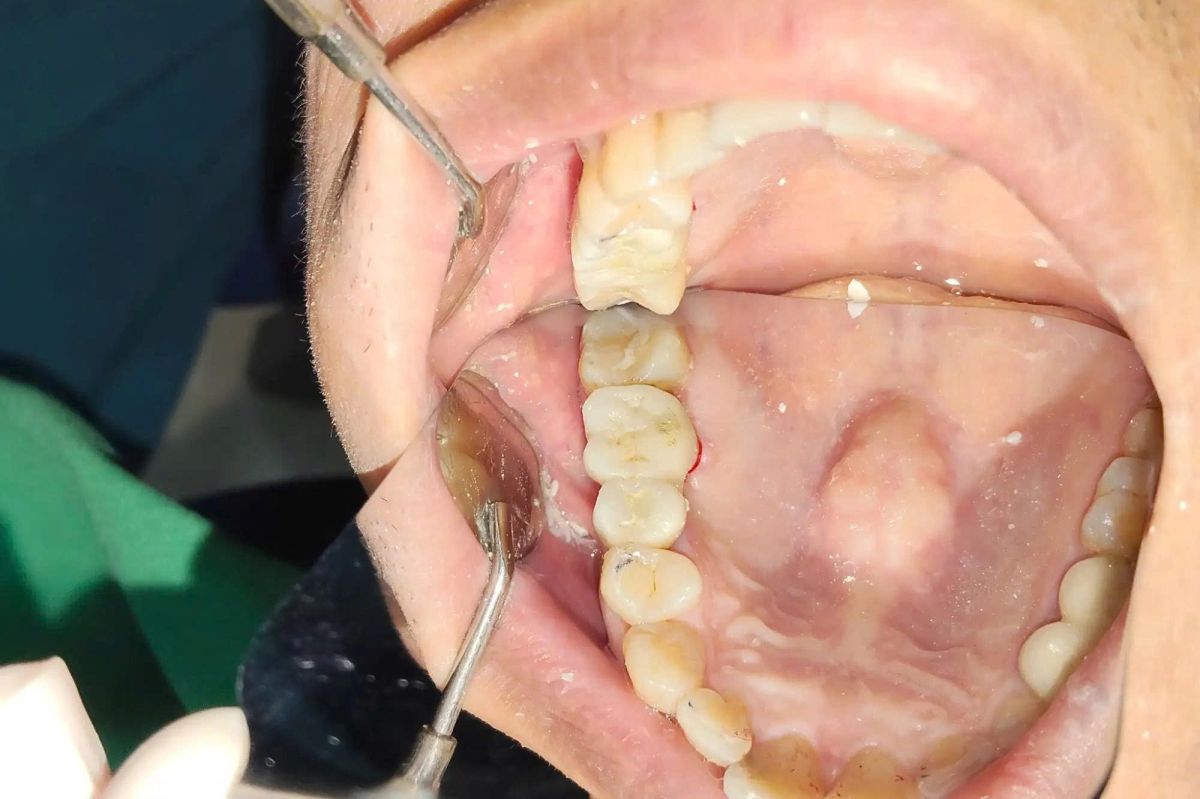

Giải pháp điều trị được chỉ định

Sau khi thăm khám lâm sàng kết hợp chụp CT 3D, bác sĩ đã xây dựng phác đồ điều trị phù hợp cho anh Quang:

Cấy ghép 2 trụ Implant Hiossen (Mỹ) tại vị trí R15 và R16

→ Thay thế hoàn toàn chân răng đã mất, phục hồi nền tảng ăn nhai vững chắc

→ Implant Hiossen có khả năng tích hợp xương tốt, độ bền cao, tương thích sinh học an toàn

Phục hình răng sứ trên Implant – gắn kết thúc

→ Tái tạo hình dáng răng hàm tự nhiên

→ Đảm bảo chức năng ăn nhai ổn định và tính thẩm mỹ hài hòa với toàn hàm

Toàn bộ quá trình được thực hiện theo quy trình chuẩn y khoa, trong điều kiện vô trùng tuyệt đối.